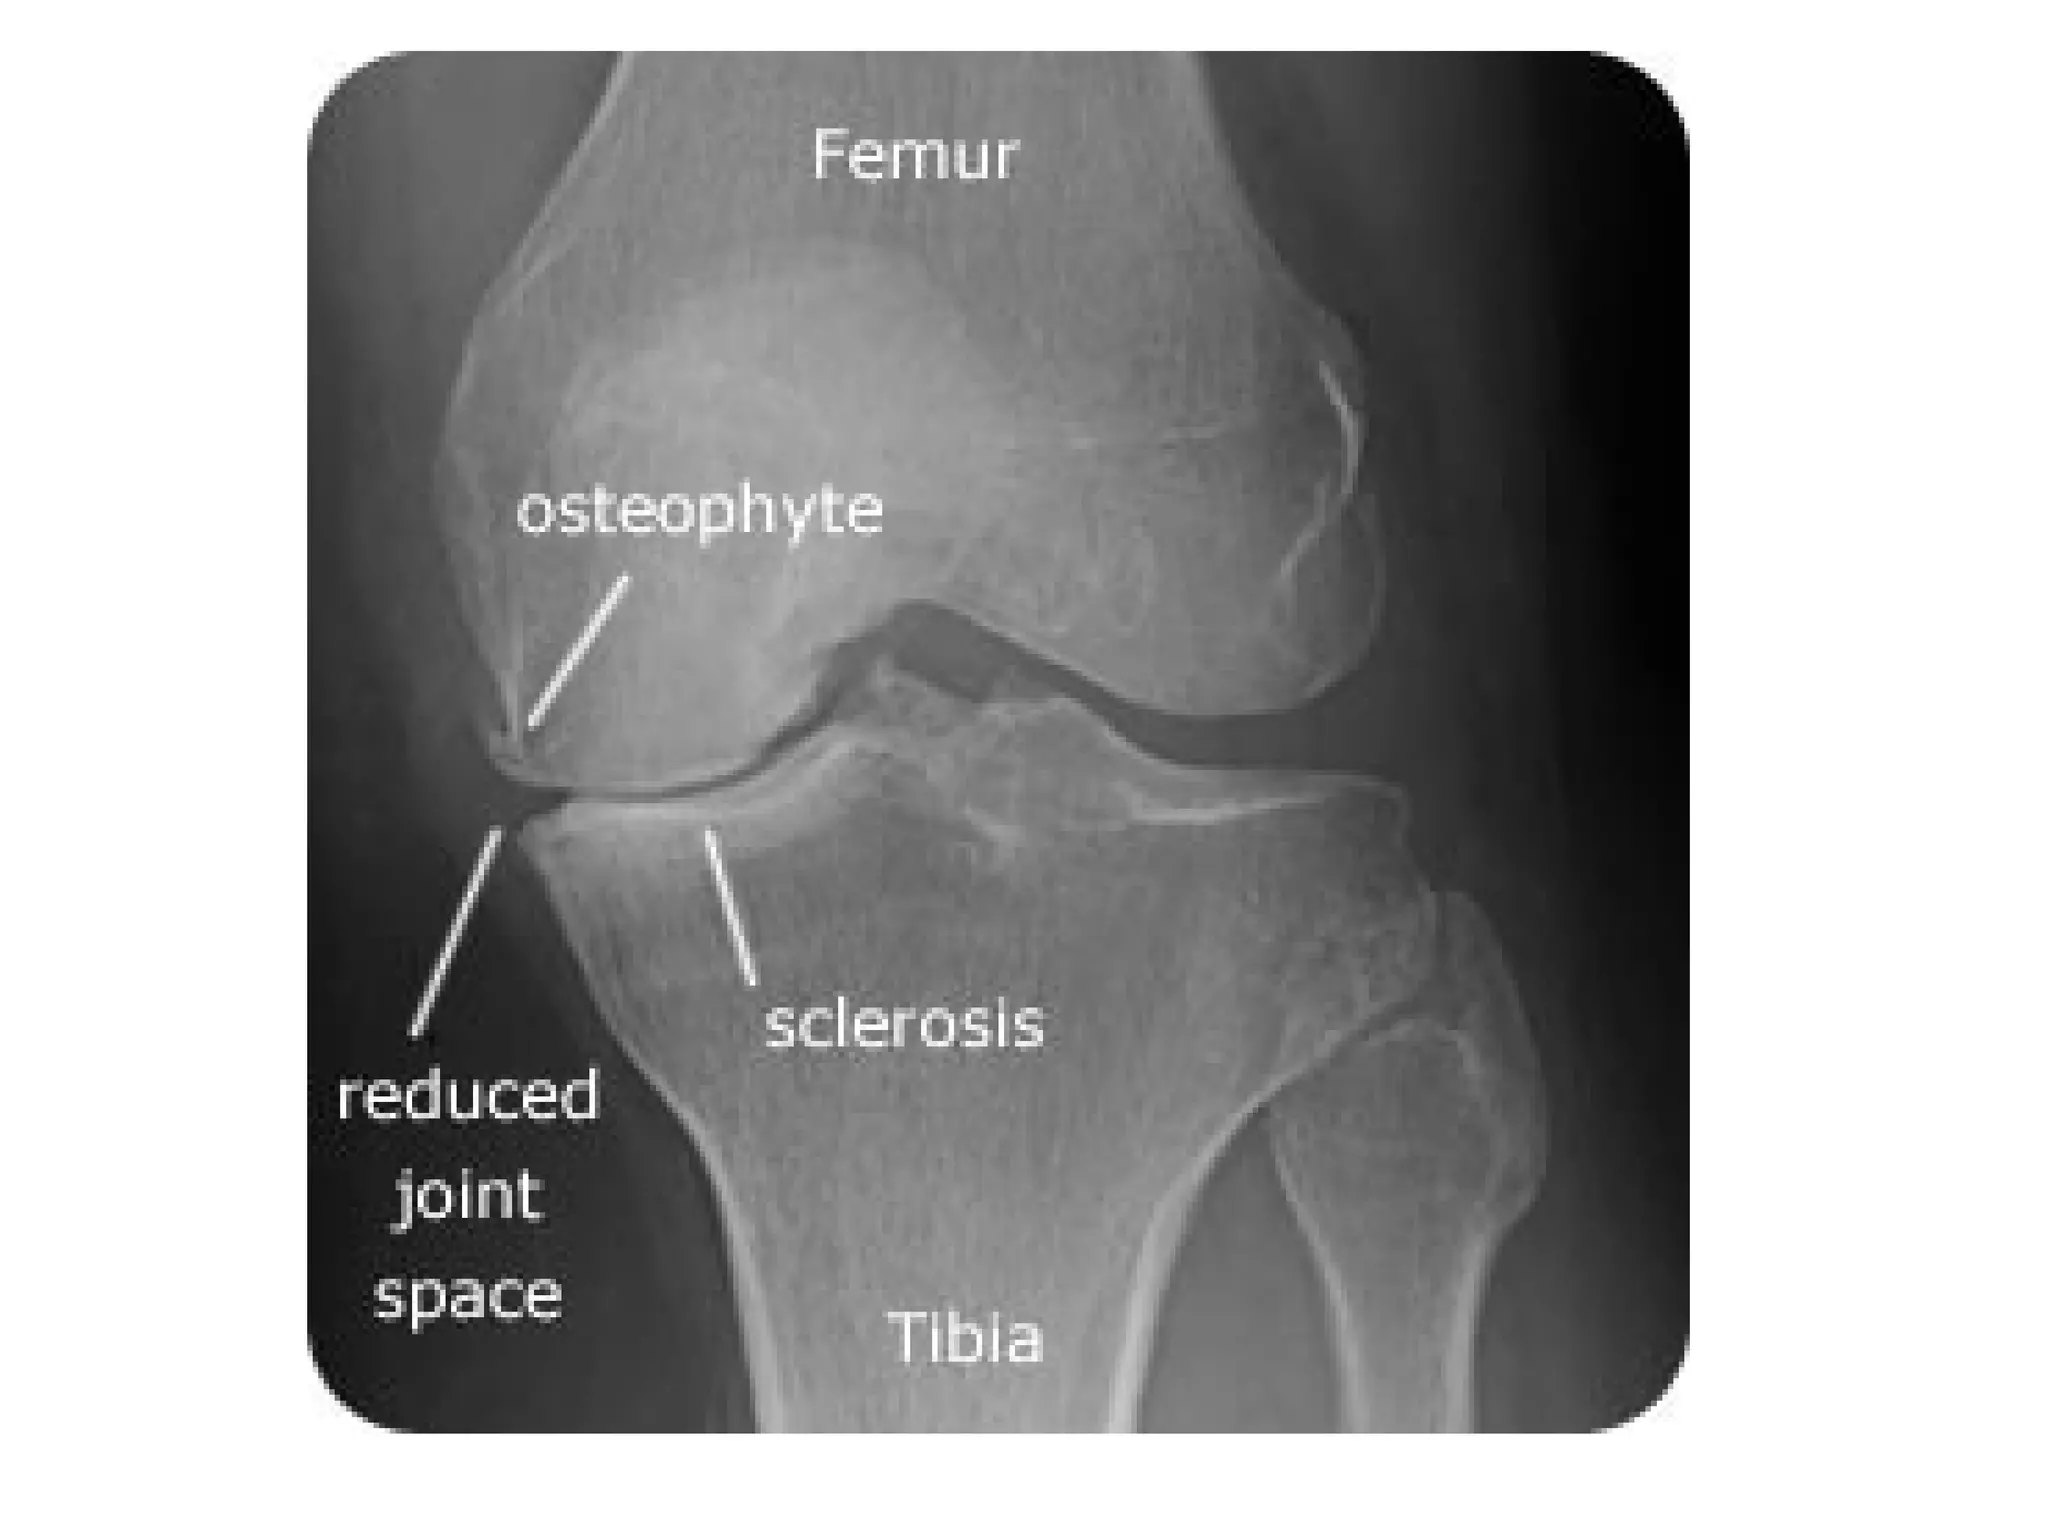

c) Radiographic Features : 5 hallmarks

1-Narrowing of joint space , usually

asymmetrical

2-Subchondral sclerosis

3-Subchondral cysts (Geode) , well-defined

lytic lesion (one of the common differential

diagnoses of a lytic epiphyseal lesions)

4-Osteophytes (bone spur)

5-Lack of osteoporosis

In the knees , primary OA predominately involves the medial tibiofemoral and

patellofemoral compartments , the asymmetric medial joint space loss (white

arrow) causes a varus deformity on standing radiographs , a large

osteophyte classically forms on the medial tibial articular margin (red

arrow) , subchondral sclerosis and cyst formation may also be found